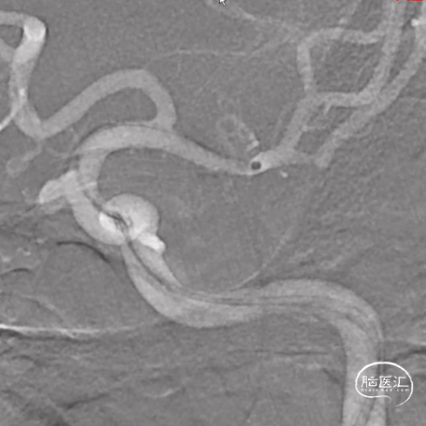

术前3D造影

建立通路,右股动脉穿刺置动脉鞘,经动脉鞘送入6F长鞘套接6F 115cm 通桥银蛇®颅内支持导管超选至左侧颈内动脉C5段,并在微导丝引导下将支架导管超选至左侧大脑中动脉M1段。

释放通桥麒麟™血流导向密网支架 4.0*20mm。

导丝按摩

术后造影,确认通桥麒麟™血流导向密网支架贴壁。

术后3D造影